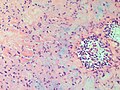

Chondromyxoid fibroma. H&E stain. | |

| LM | spindle cells or stellate cells in a myxoid or chondroid stroma, lobules with hypocellular centers and hypercellular peripheries, +/-giant cells in the hypercellular periphery, scattered calcifications, no true hyaline cartilage formation, no mitotic activity |

Features:[3]

- Spindle cells or stellate cells in a myxoid or chondroid stroma.

- Lobules with hypocellular centers and hypercellular peripheries.

- Giant cells in the hypercellular periphery.

- Scattered calcifications.

- No true hyaline cartilage formation.

- No mitotic activity.